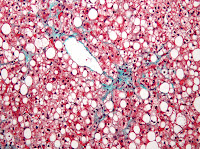

![]() |

| Too much of a good thing? Micrograph of non-alcoholic fatty liver disease, caused by the same kind of lipid accumulations M-Shirazi et al. observed in rats after receiving high dose fish oil supplements in a 2011 study (learn more) |